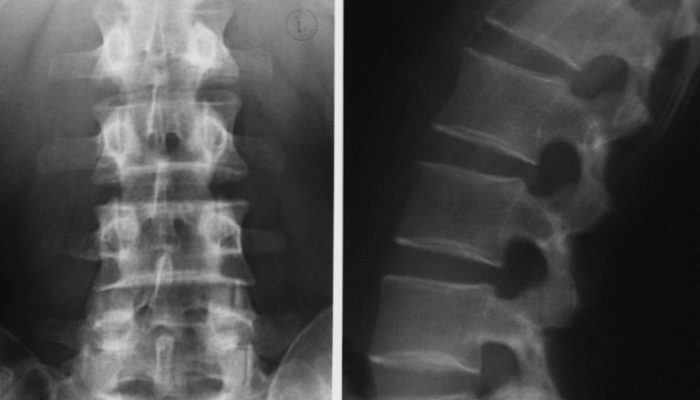

Дифференцировать вертеброгенную боль в ноге нужно с другими распространенными причинами: сосудистыми, ортопедо-травматическими, воспалительными, эндокринными. Для этого врач, кроме клинической картины, ориентируется на результаты дополнительных исследований, позволяющие сформировать целостное восприятие проблемы. Пациенту назначаются такие диагностические процедуры:

- Рентгенография позвоночника.

- Томография (компьютерная и магнитно-резонансная).